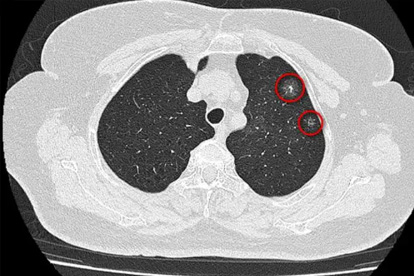

肺癌是一种常见的恶性肿瘤,其发病原因复杂,包括吸烟、空气污染、职业暴露等多种因素。早期诊断和规范治疗对提高患者生存率至关重要。

广州市胸科医院在肺部疾病诊疗方面具有专业特色,对肺癌的诊断和治疗积累了丰富经验。医院开展支气管镜检查、CT引导下肺穿刺活检等诊断技术,以及肺癌的综合治疗。